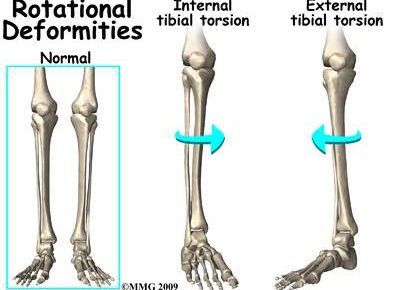

こんにちは!横浜本牧パーソナルトレーナー宮原崇です。 明日は節分ということで、父親の役割は決まって鬼役なのでコンディションを良くしていきたいと思います。 さて、昨日はもも裏の筋肉である大腿二頭筋が何しからの問題を起こすと…

こんにちは!横浜本牧パーソナルトレーナー宮原崇です。 今日は夏晴れでセミの鳴き声も心地よいです。 さて、午前のトレーニングセッションを終えてこれから午後の部となりますが、ひざ痛の方の多くが持っている身体の特徴をお伝えいた…